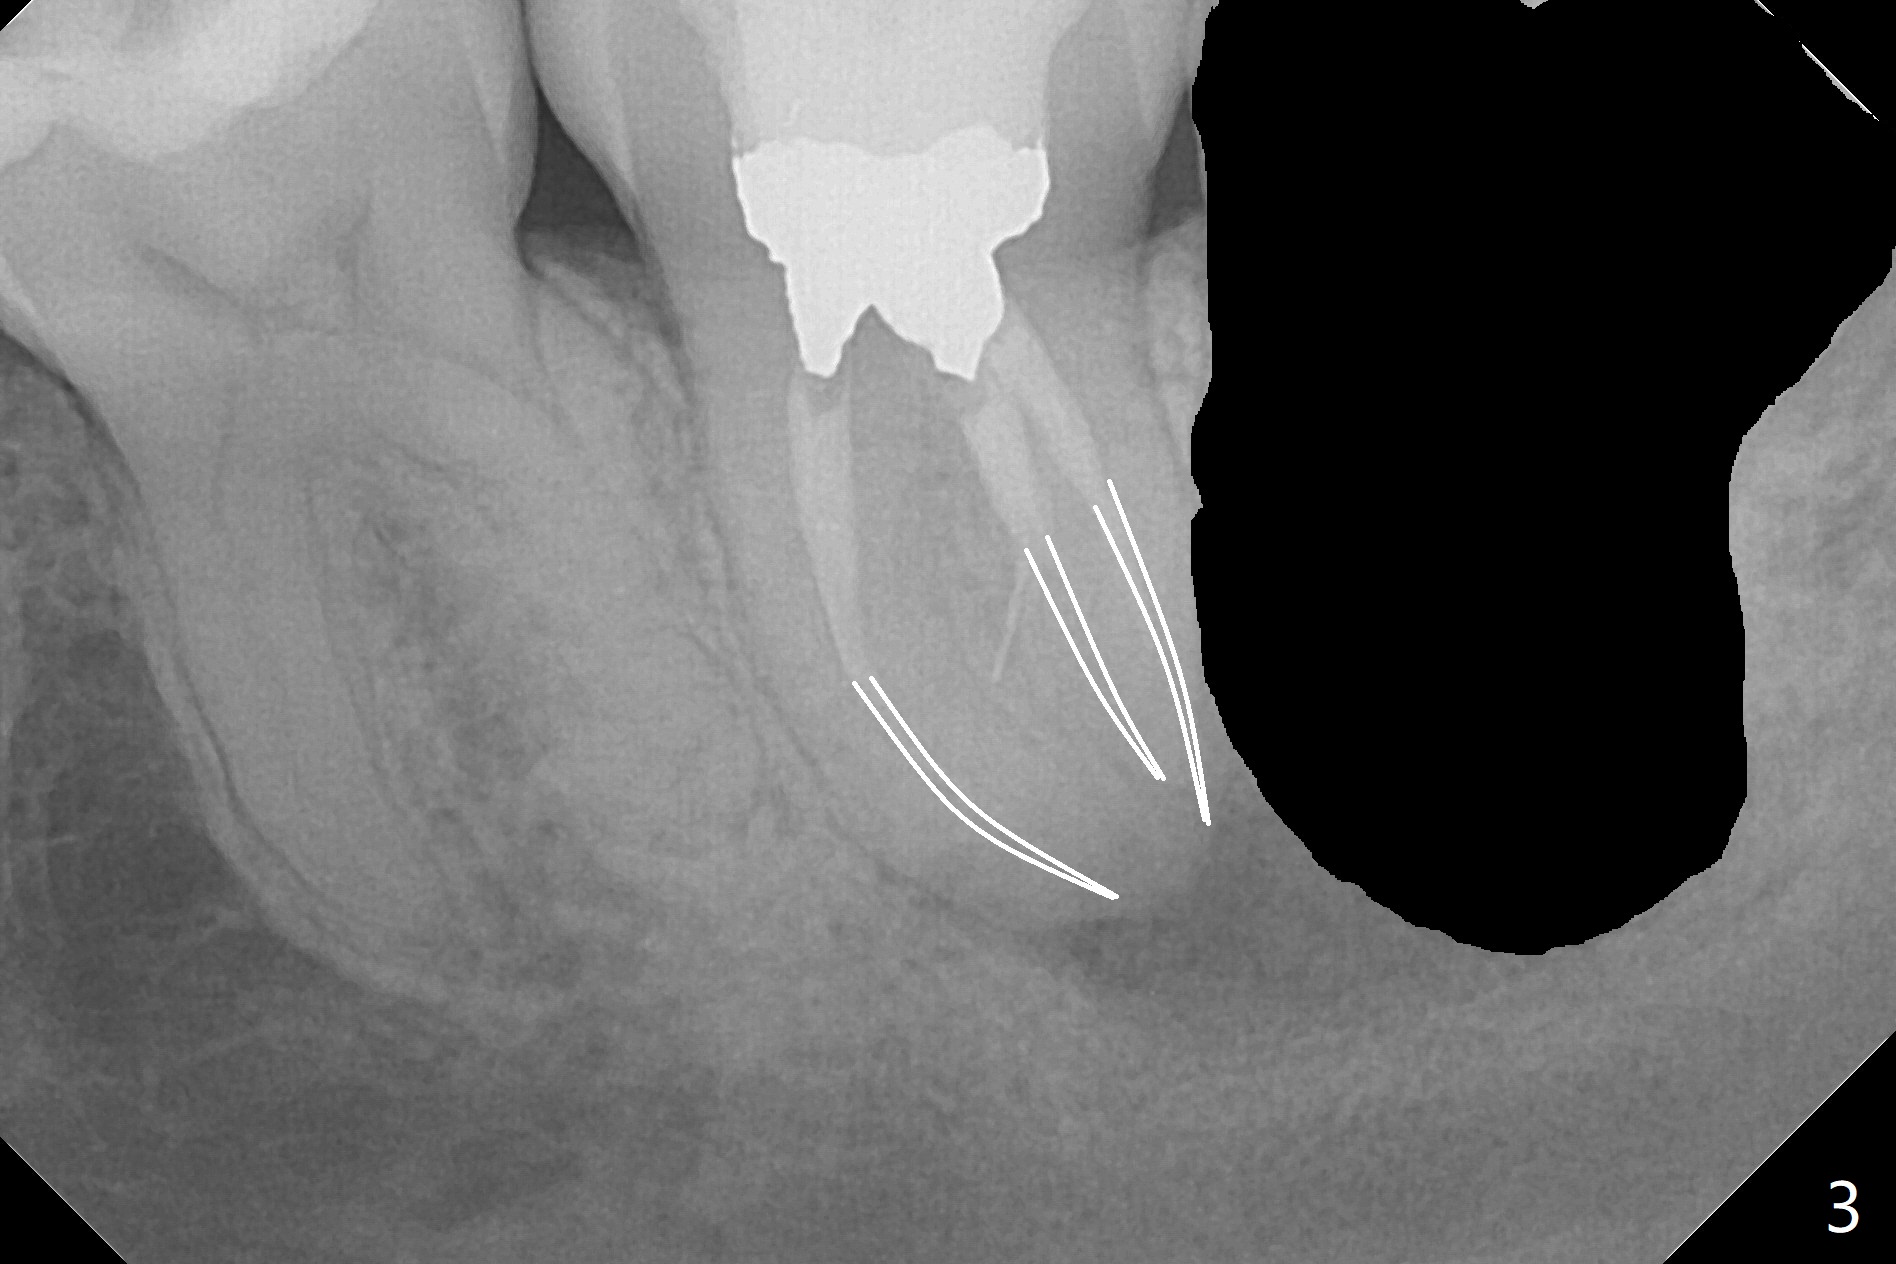

A 37-year-old woman requests extraction of the 3rd molars and orthodontic retreatment (Fig.1). Since the bone between #17 and 18 is thin and short (Fig.2 black *), bone graft is needed after #17 extraction. But the apical infection at #18 (Fig.2 white *) may affect graft survival. The patient agrees to have RCT retreatment done (Fig.3 white curved lines) before extraction (black area). The apical granulation tissue can be removed (Fig.4 red area) prior to bone graft (Augma). The latter will be also placed at #17 as a control. After endodontic consultation, the patient does not want RCT retreatment. She would like to have the 3rd molars extracted first and #18 removed if needed. After #17 extraction (Fig.5), apicoectomy will be performed at #18 (Fig.6 (white outline: surgical bur, use non-torque handpiece)). Following curettage of the apical lesion at #18 (Fig.7), bone graft will be placed (Fig.8 red circles). In fact the patient insists upon #1, 16, 17, and 32 extraction. After extraction, allograft (Fig.9 A (Ossogen, Mineralized Cort/Can (30%/70%), .25-1.0 mm) is placed in the mesioapical of the sockets of #17 and 32, while Osteogen Plug (O) and BioXclude in the distocoronal one (4-0 PGA suture). There is minimal bone between the 2nd and 3rd molars (black arrowheads). The allograft is intentionally pushed into #18 apical defect after enucleation (white arrowhead). The sockets are slightly open, although sutures are in place 2 weeks postop (Fig.10,11). It is unknown whether the bone graft is partially dislodged or not.